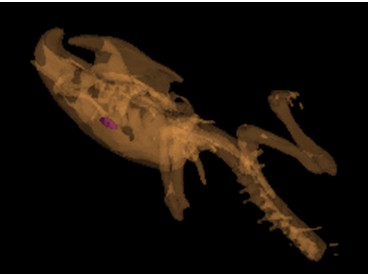

圖 4 裸鼠腫瘤和臟器分割后三維重建顯示的結(jié)果

從圖4可以明顯的看到腫瘤在小鼠體內(nèi)的分布情況,胃癌腫瘤轉(zhuǎn)移到肝上的三個微小腫瘤的體積分別為0.7767mm3、1.1125 mm3、1.1261mm3、在腎中的腫瘤體積為20.2666 mm3。解剖后實測結(jié)果與micro-CT掃描結(jié)果一致。